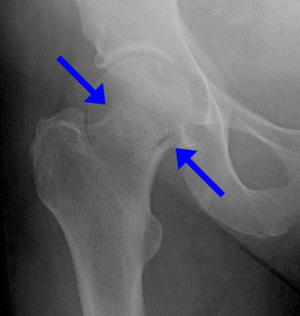

GÃY CỔ XƯƠNG ĐÙI

Gãy cổ xương đùi là một bệnh rất thường gặp ở những người già, nhất là phụ nữ.

Cổ xương đùi là phần nối tiếp giữa chỏm và thân xương đùi. Nó chịu một lực tải rất lớn từ trên cơ thể xuống. Cấu trúc giải phẫu cổ xương đùi rất đặc biệt, nó có ba bè xương đan chéo nhau để chịu sức căng lên cổ xương đùi. Tuy nhiên giữa ba bè xương này lại có một điểm khuyết hình tam giác gọi là tam giác Ward. Đây là điểm yếu nhất của cổ xương đùi nên hay bị gãy chổ này. Ngoài ra, ở những người già còn có trình trạng loãng xương kèm theo. Xương loãng sẽ bị giòn và yếu nên cũng dễ gãy nếu có một chấn thương xảy ra.